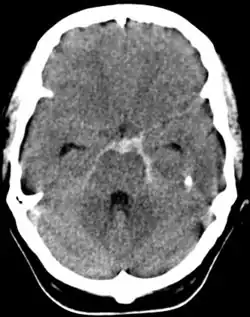

Image scannographique d'une hémorragie méningée

Il est systématique et demandé en urgence : il permet de faire le diagnostic en décelant des hyperdensités au sein des espaces sous-arachnoïdiens (témoignant de la présence de sang frais) de topographie variable selon l'étiologie et la localisation d'une lésion éventuelle (vallée sylvienne, scissure inter-hémisphérique, citernes de la base, sillons de la convexité). La sensibilité est excellente dans les premiers jours[11]. Il recherche des complications (hématome cérébral, inondation ventriculaire, hydrocéphalie aiguë). Cette hyperdensité peut s'amoindrir, voire s'escamoter complètement après quelques jours d'évolution[5].